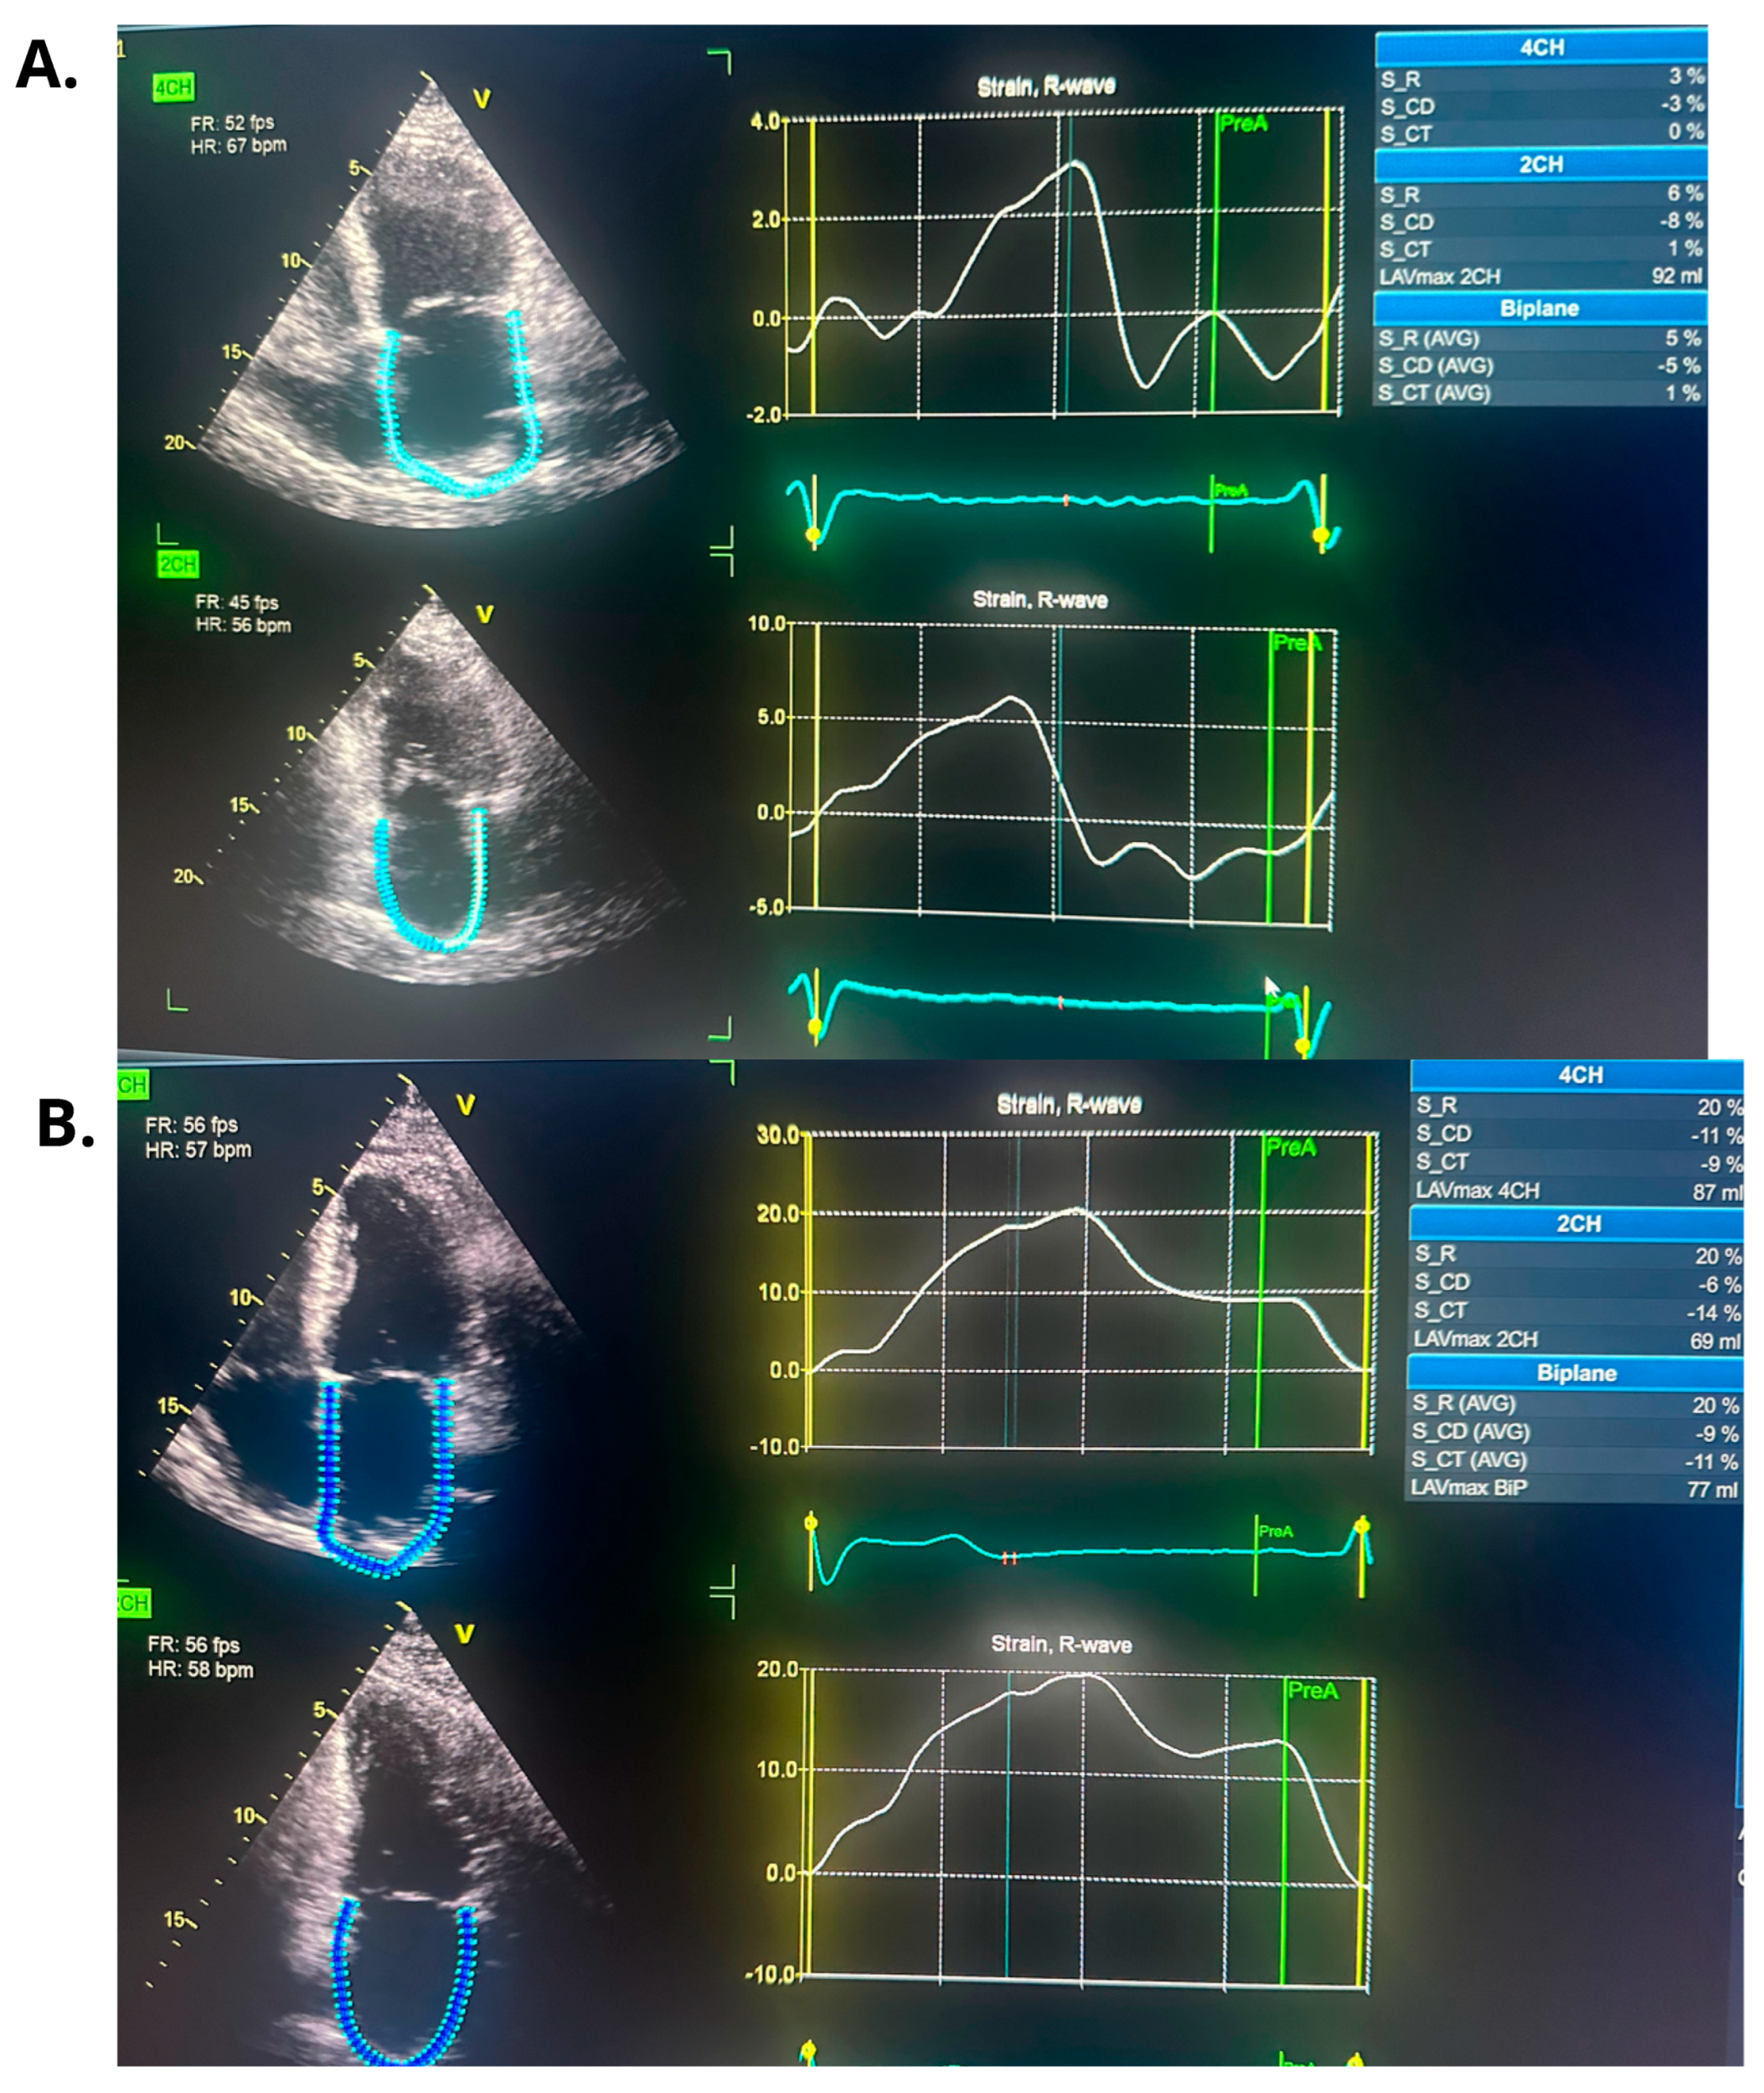

| Echocardiographic Parameters | First Admission | Ablation | Follow-Up |

|---|---|---|---|

| PALS (%) | - | 5 | 20 |